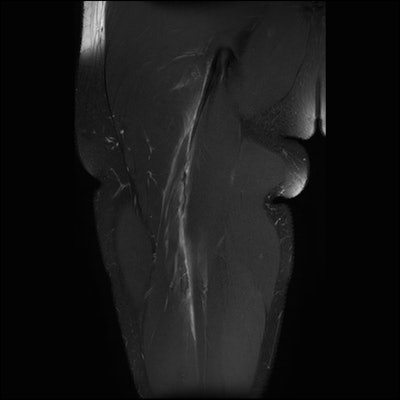

AFL (Australian Football League) football, rugby, and netball account for most injuries -- much more than, say, soccer, basketball, and cricket. As the physical demands of these sports have changed, we see many more muscle injuries (particularly hamstring and calf) than before. In the last five years, we have seen more women transition over to football and rugby. As a consequence, we are seeing many more injuries in the female population than before; these include muscle tears, shoulder dislocations, and anterior cruciate ligament (ACL) rupture. The incidence of ACL rupture in AFL football for women is nine times that of the male population, which is quite worrisome.

As a diagnostic tool, MRI has superseded both ultrasound and radiographs. For example, we typically perform 80 musculoskeletal MRI scans per day but perhaps fewer than 10 radiographs. There is a broad mix of all the joints. We are now quite confident in assessing muscle injuries and providing accurate information about when an athlete might return to play and the risk of a recurring injury. For intervention, fluoroscopy has become redundant, and we would typically perform 50 to 60 interventions per day under ultrasound or CT guidance.